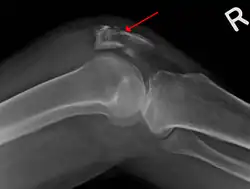

Fracture de rotule

La radiographie déterminera s'il y a oui ou non bel et bien une fracture de la rotule. Si oui, le chirurgien orthopédiste pourra décider d'opérer.